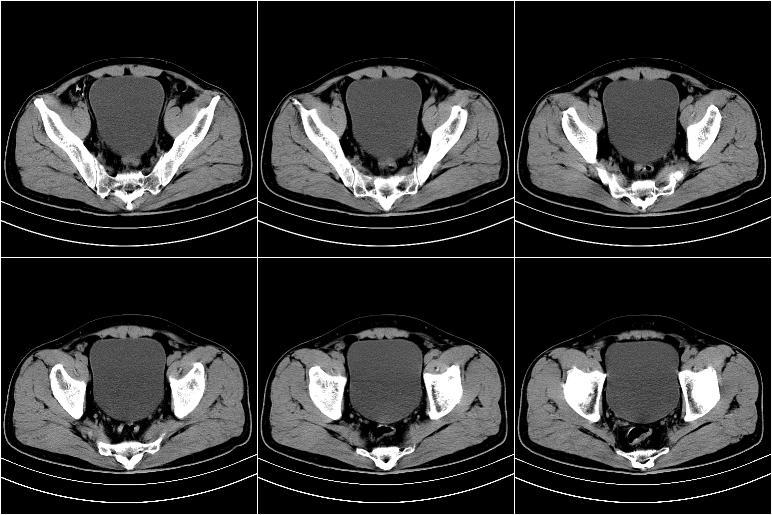

标题: CT21569:M,54Y,右侧中腹部疼痛,IVP示右侧输尿管中下段充盈缺 [打印本页]

标题: CT21569:M,54Y,右侧中腹部疼痛,IVP示右侧输尿管中下段充盈缺

右输尿管下段扩张积水。左下腹部肠管间质瘤不除外。

右侧输尿管扩张积水,考虑结石,最好做个增强除外输尿管占位性病变

支持右侧输尿管中下段扩张积水,建议增强排除占位。

ct21569和ct21569b(增强)结果:阑尾腺癌,侵犯回盲部及输尿管中段。手术切除部分升结肠、回肠及受侵4cm之输尿管,做回-横结吻合,输尿管支架置放术并吻合,术后病理腺癌,阑尾来源可能性大。

右侧输尿管扩张似见软组织密度影,输尿管占位不能排除。